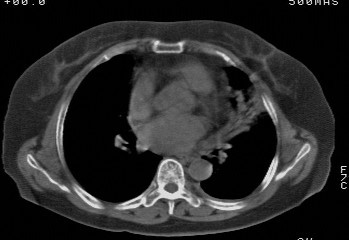

f,74发热咳嗽三天

考虑左肺上叶中央型肺癌并左肺上叶舌段肺不张。

考虑左肺上叶中央型肺癌并左肺上叶舌段肺不张.

左肺上叶舌段肺不张,建议作进一步检查除外中心型肺癌。

左肺上叶舌段肺不张,建议行纤支检查除外中心型肺癌。支持!